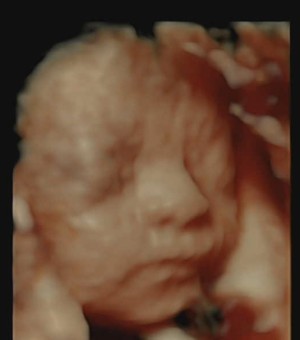

30주 입체초음파입니다 :)

이레IYRAE

2025-08-21

4

0